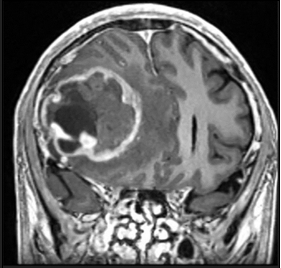

A 51-year-old male with a medical history of Neurofibromatosis type 2 presented with a clinical progression spanning 3 months, characterized by difficulties in concentration, short- term memory loss, and a frontal oppressive-type headache rated 5/10 on the analog pain scale, exacerbated by the Valsalva maneuver. Imaging studies revealed a hypodense lesion with central necrosis in the right frontal lobe accompanied by perilesional edema, resulting in interhemispheric line displacement. Additionally, there was partial collapse of the ipsilateral lateral ventricle and subfacial herniation.

Gimson and Smith's study documented epileptic seizures detected on anesthetic depth monitors with EEGp, predominantly utilizing BIS in the literature.16 You et al. demonstrated SedLine's effectiveness in detecting epileptiform discharges with 100% sensitivity and specificity, emphasizing its utility in identifying abnormal brain activity.17 Regarding anesthetic drugs, no clear dose-response relationship exists for seizures, and some drugs may have pro-epileptic effects, emphasizing careful consideration in patients with seizure history or predisposition.18 Early seizures post-craniotomy for brain tumor resection are common, warranting vigilance and appropriate management to prevent and address potential complications (Figure 1-4).19-21

Figure 1 Preoperative tomography, coronal view.

Figure 2 Preoperative tomography, axial view.